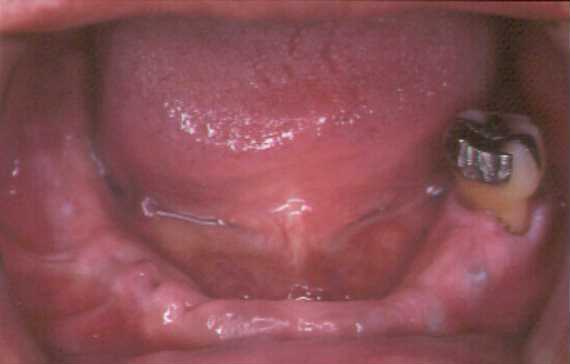

下顎オーバーデンチャー

1本を残して後は欠損

4本インプラント植立ごの支台

各支台を連結

その上に義歯をのせる